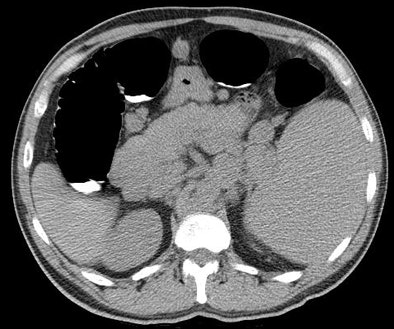

| Image demonstrates splenomegaly and massively enlarged lymph nodes in a patient with unsuspected non-Hodgkin's lymphoma. |

As for extracolonic lesions, the mean patient age (61.3 years) was similar to the general cohort, and gender (19 women, 17 men) did not differ greatly from the entire group. The most common extracolonic primary cancers were renal cell carcinoma (n = 11, including 10 stage I), followed by lung cancer (n = 8, including three stage I, one stage II, three stage II) and non-Hodgkin's lymphoma (n = 6). In addition, two patients had prostate cancer and two had localized adrenal cancers. Some of the other cancers detected included a breast cancer, a stromal cancer in the stomach, a carcinoid tumor in the appendix, and a stage I adrenocortical carcinoma.

"Our findings show that unsuspected cancer is found on average more than once every 200 adults screened, and most are extracolonic malignancies," the authors wrote. "At first glance, it may seem paradoxical that extracolonic cancers outnumber invasive CRC given the indication and focus of the examination. However, CRC was still the predominant cancer identified, followed by renal cell carcinoma, bronchogenic carcinoma, and non-Hodgkin's lymphoma."